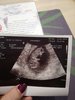

I ja po wizycie. Bobo ma 3,2 cm, wielkością jest na równo 10tc, termin na 14.09 :) Wyniki ok. Tłumaczyć Wam nie będę co z tą toxoplazmozą, bo do dość skomplikowane ale jest wszystko pod kontrolą :)

• USG.jpg

USG.jpg

349,8 KB · Wyświetleń: 115